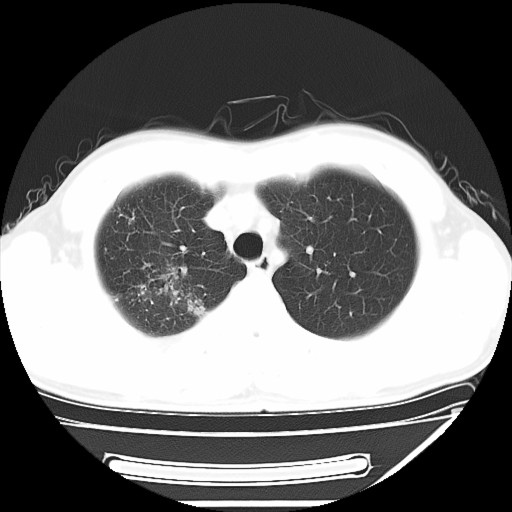

男,32岁,多年前右上肺结核,近期胸部不适,ct检查次序如上,上传主要层面,纵隔未见明显肿大淋巴结。

2008年12月20日:

本人初次(2008年12月20日ct片)诊断为右上肺结核伴右侧胸水!保守治疗后,遂复查ct胸水逐渐减少!最后(2009年05月18日)诊断为右上肺结核,右侧胸水吸收后伴包裹形成!从逐次ct检查上看,胸水吸收好转,只是从2009年05月18日ct片看到一个胸膜结节。临床医生及某肿瘤医院认为2009年05月18日ct片,右后胸壁结节,考虑为胸膜肿瘤!